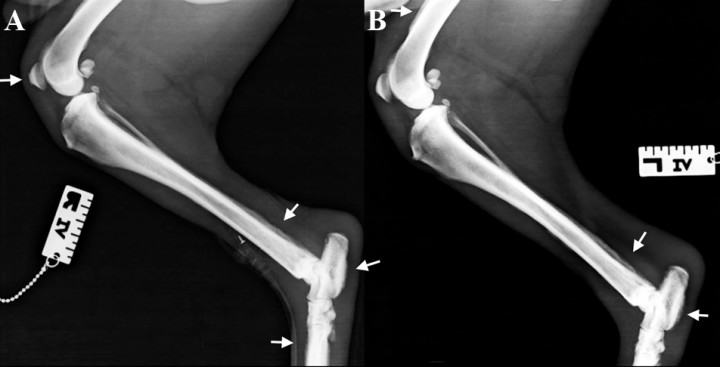

<p>Proyección mediolateral de cúbito y radio. <strong>(A) </strong>Derecha. <strong>(B) </strong>Izquierda.</p>

Proyección mediolateral de cúbito y radio. (A) Derecha. (B) Izquierda.

<p>Mismas radiografías de la Figura 2. Se observa reacción perióstica del tipo en empalizada (ver flechas) con afectación del aspecto dorsal y palmar del cuerpo de los huesos metacarpianos y del proceso accesorio del carpo, de la cara craneal de la epífisis distal y de la diáfisis del radio, del borde caudal de la diáfisis distal del cúbito y del margen craneal y caudal del tercio distal del húmero. No hay afectación de las superficies articulares ni destrucción ósea. Se aprecia la tumefacción de los tejidos blandos.</p>

Mismas radiografías de la Figura 2. Se observa reacción perióstica del tipo en empalizada (ver flechas) con afectación del aspecto dorsal y palmar del cuerpo de los huesos metacarpianos y del proceso accesorio del carpo, de la cara craneal de la epífisis distal y de la diáfisis del radio, del borde caudal de la diáfisis distal del cúbito y del margen craneal y caudal del tercio distal del húmero. No hay afectación de las superficies articulares ni destrucción ósea. Se aprecia la tumefacción de los tejidos blandos.